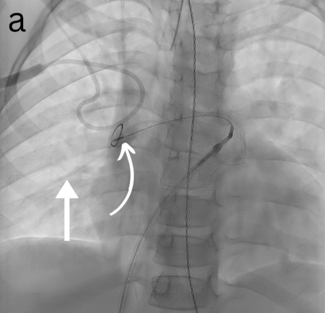

Charles Gallen, MD; Amine Boussofara, MD; Quentin Landolff, MD

A 67-year-old man who was overweight, hypertensive, and had no cardiovascular medical history was treated for a lateral myocardial infarction due to a ramus coronary branch occlusion.